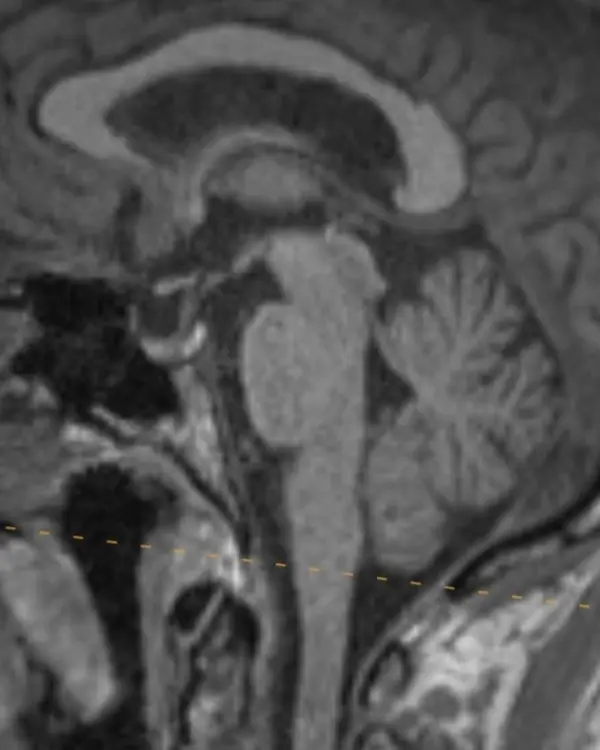

The brainstem, outlined in a white dotted line, is divided into the midbrain, pons, and medulla. Each segment has a characteristic appearance that is easiest to recognize in the sagittal plane.

Notice the beak-shaped anterior margin of the midbrain and the cerebrospinal fluid (CSF) space underneath it.

The pons has a bulbous contour anteriorly and a triangular shaped CSF space posterior to it.

The medulla is thin, gradually blends in appearance with the cervical spinal cord, and has a small CSF channel posterior to it.